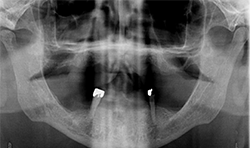

A 69-year-old male presented with an existing maxillary full denture and mandibular fixed partial denture (Tooth Nos. 22-27) with pain and suppuration on abutment teeth supporting the FPD (Figs. 7, 8). All existing abutment teeth were carious and periodontally involved. It was decided with the patient the best treatment option would be to extract the remaining mandibular teeth. All options were presented to patient and patient desired a fixed hybrid for both arches.

Fig.7